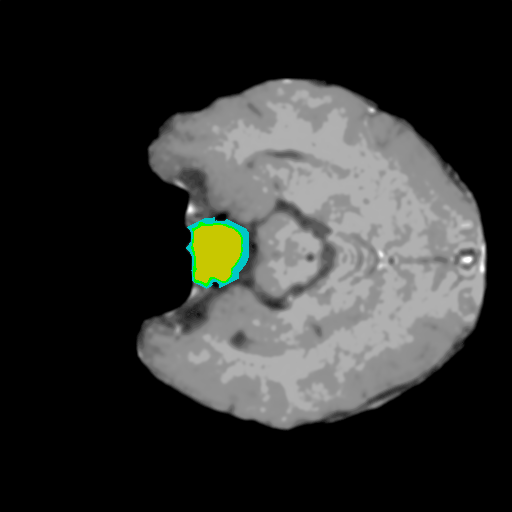

Extensive experiments have been performed in the current setup, and experimental outcomes are reported with the demonstration of numerical and statistical analyses using the proposed QFS-Net, QIS-Net [39], convolutional U-Net [18] and Residual U-Net (URes-Net) architectures [20]. The human expert segmented skull-tripped contrast enhanced DSC brain MR input image slices of size and ROIs are provided in Figure 5 as samples. The demonstration of QFS-Net segmented images followed by the essential post-processed outcome on the slice no. for class level with four distinct activation schemes () are shown in Figure 6. It is evident from the experimental data provided in Table LABEL:tab1 that the proposed QFS-Net performs optimally for the -connected quantum fuzzy pixel information heterogeneity assisted activation () with and gray scale set in comparison with other thresholding schemes and gray scale sets under the four evaluation parameters () [44]. The segmented tumors obtained using the proposed self-supervised procedure under class transition levels with four different thresholding schemes , , and are demonstrated in Figures 7- 8 for the class boundary sets and [39], respectively. The segmented images using the remaining two class boundary sets ( and ) [39] are provided in the supplementary materials section. The segmented ROIs describing the whole tumor region after the masking procedure using QIS-Net, U-Net and URes-Net are also reported in Figure 9.